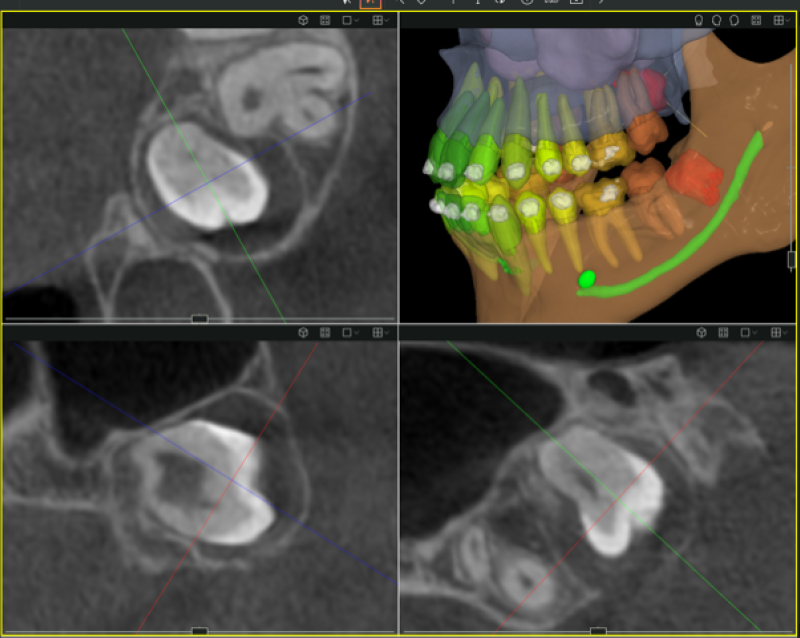

Für eine exakte Diagnose Ihrer Zahngesundheit sind detaillierte Bilder unverzichtbar. 2D-Röntgenbilder geben einen guten Ein- und Überblick über Ihre Zähne und Knochenstrukturen. In komplizierteren Fällen liefert die 3D-Diagnostik tiefere Einblicke, etwa bei Implantaten, Weisheitszähnen, Wurzelkanalbehandlungen oder Kiefergelenkproblemen.

Für die 2D-Diagnostik wird ein klassisches Röntgenbild erstellt, das in wenigen Sekunden verfügbar ist. Bei der 3D-Diagnostik erfolgt eine Rundum-Aufnahme mit modernster Röntgentechnik, die detaillierte Schichtbilder von Kiefer und Zähnen erzeugt. Beide Verfahren sind schnell, vollkommen schmerzfrei und sicher.

Durch 2D- und 3D-Diagnostik erhalten wir ein umfassendes Bild Ihrer Zahn- und Kiefersituation. Dadurch können wir frühzeitig Probleme erkennen, Behandlungen präziser planen und Ihnen unnötige Eingriffe ersparen. Die hohe Genauigkeit der 3D-Bilder bietet insbesondere bei komplexen Eingriffen eine optimale Behandlungsgrundlage.